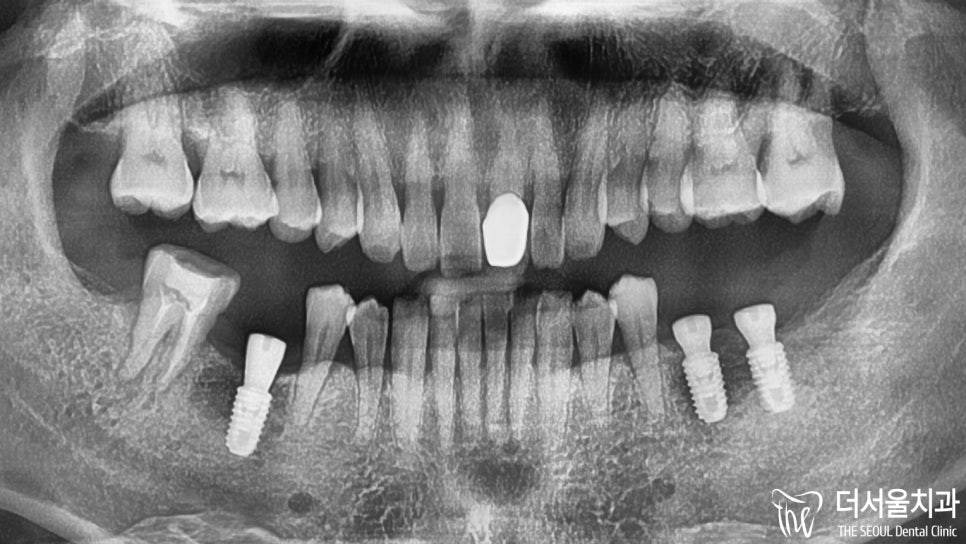

더 서울에서 정확한 진단을 위해

엑스레이 촬영을 진행한 결과,

하악 우측 잔존 어금니는 심한 충치로 인해

병소가 치수까지 감염되어 있었습니다.

디지털임플란트 를 제일 먼저 하기로 했기 때문에

정확한 식립을 위한 분석을 시작했습니다.

빠져있는 아래 어금니 세 곳에

인공치를 심기로 했었는데요.

세 곳 모두 주변 조직 및 인접치와의 관계를

각각 파악하여 최적의 식립로를 설정했습니다.

이후, 미리 제작된 가이드를 사용하여

무절개 방식으로 단단하게 심어드렸습니다.